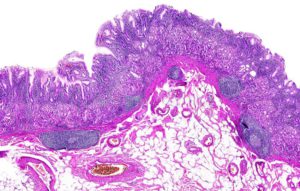

Хронічний гастрит у людини - Грижа.

Хронічний гастрит у людини